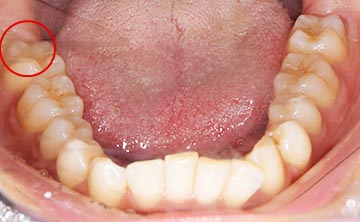

抜くと痛い親知らずとは

麻布十番歯科で親知らずが横向きに生えている症例のレントゲン写真のイメージ

親知らずを抜くのに痛みを伴いやすいものが写真とレントゲンにあるような真横にはえているもの、もしくは斜め下にはえている下顎の親知らずです。また、根が曲がっていたり、数が多いほど抜くのが難しい経口にあります。

この場合、歯ぐきを切ったり、歯を囲っている周りの骨を削って抜いていかなければなりません。

そのため、抜歯後は腫れや痛みが伴いやすくなります。 抜歯中は麻酔を行いますが、骨が硬い方は麻酔がなかなか効かないこともあります。そのため痛みを伴うことがあります。